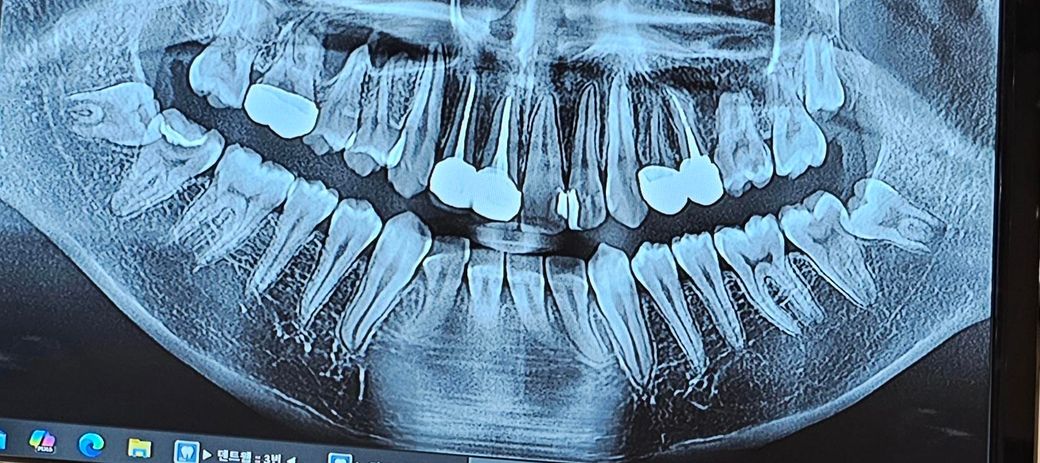

이 치아는 신경치료 해야하는 치료인가요?

사진기준 맨 왼쪽치아요

근데 제가 2주뒤면 군대를 가서 신경치료를 못받는 상황이거든요.. 근데 들은말로는 충전제밑에 충치가 커보이고 신경치료 확률이 높다 이래서요..

엑스레이 상으로 충치가 깊어 보이긴 합니다. 군대를 가야된다면 일단은 임시재료로 매꿔놓고 추후에 시간이 되면 신경치료를 하시는게 좋을것같습니다.

사진상으로는 신경치료 가능성이 높습니다. 군대 가기전에 치료를 마무리하심이 좋아보입니다.